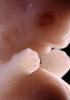

Carnegie Stage 19 (47 post-ovulatory days)

Most embryos at stage 19 are approximately 47-48 post-ovulatory days old and measure 17-20 mm in length. Distinguishing criteria for this stage include straightening of the trunk, the limbs extend nearly directly forward, toe rays are prominent, but interdigital notches have not yet appeared in the foot.

Although some of the photographs below show abnormal embryos, the animations and MRI slice images all depict normal embryos. Abnormal embryos are noted in the titles of the large photos when they are opened.